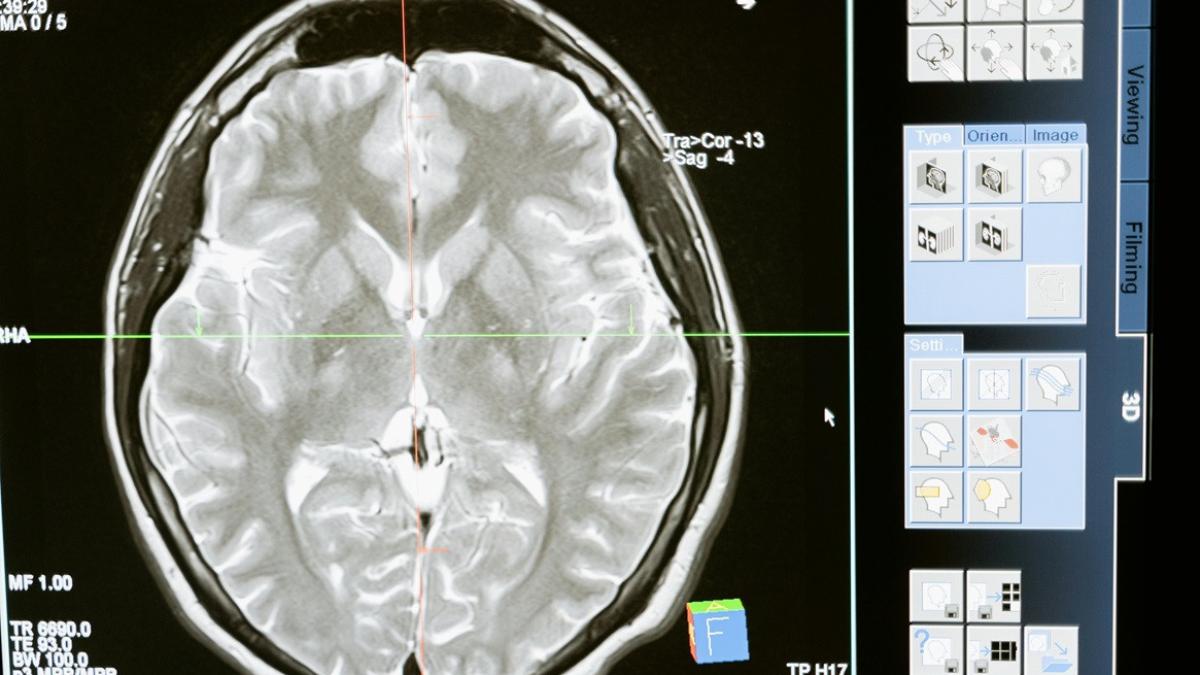

Te-ai gândit vreodată cum ar fi să folosești telefonul fără să-l atingi? Să trimiți un mesaj fără să tastezi? Să aprinzi lumina fără să te ridici din pat? Toate acestea devin posibile datorită unei tehnologii care, până nu demult, părea desprinsă din filmele SF: interfața creier–computer.

Este un dispozitiv care se conectează direct la creierul uman și „traduce” gândurile în comenzi digitale. Cu alte cuvinte, creierul trimite un semnal – de exemplu, „vreau să mișc cursorul pe ecran” – iar dispozitivul îl interpretează și îl transmite către un computer, telefon sau alt aparat.

Această tehnologie este folosită în special pentru a ajuta persoanele cu paralizie sau alte afecțiuni neurologice grave. De exemplu, cineva care nu-și poate mișca mâinile poate, cu ajutorul unui implant cerebral, să scrie un mesaj, să navigheze pe internet sau chiar să controleze o proteză robotică.